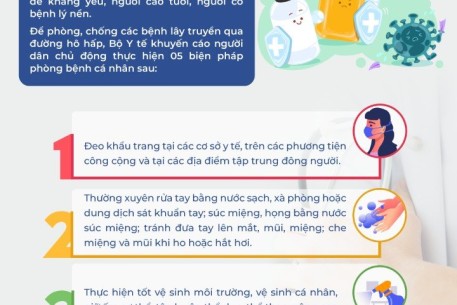

05 BIỆN PHÁP PHÒNG, CHỐNG CÁC BỆNH LÂY TRUYỀN QUA ĐƯỜNG HÔ HẤP

20:52 12/12/2023

Hiện nay đang trong giai đoạn vào mùa Đông Xuân, thời tiết chuyển mùa thay đổi thất thường là nguyên nhân xuất hiện và lây lan các dịch bệnh truyền nhiễm, nhất là bệnh lây truyền qua đường hô hấp, tiềm ẩn nguy cơ bùng phát các dịch bệnh truyền nhiễm.